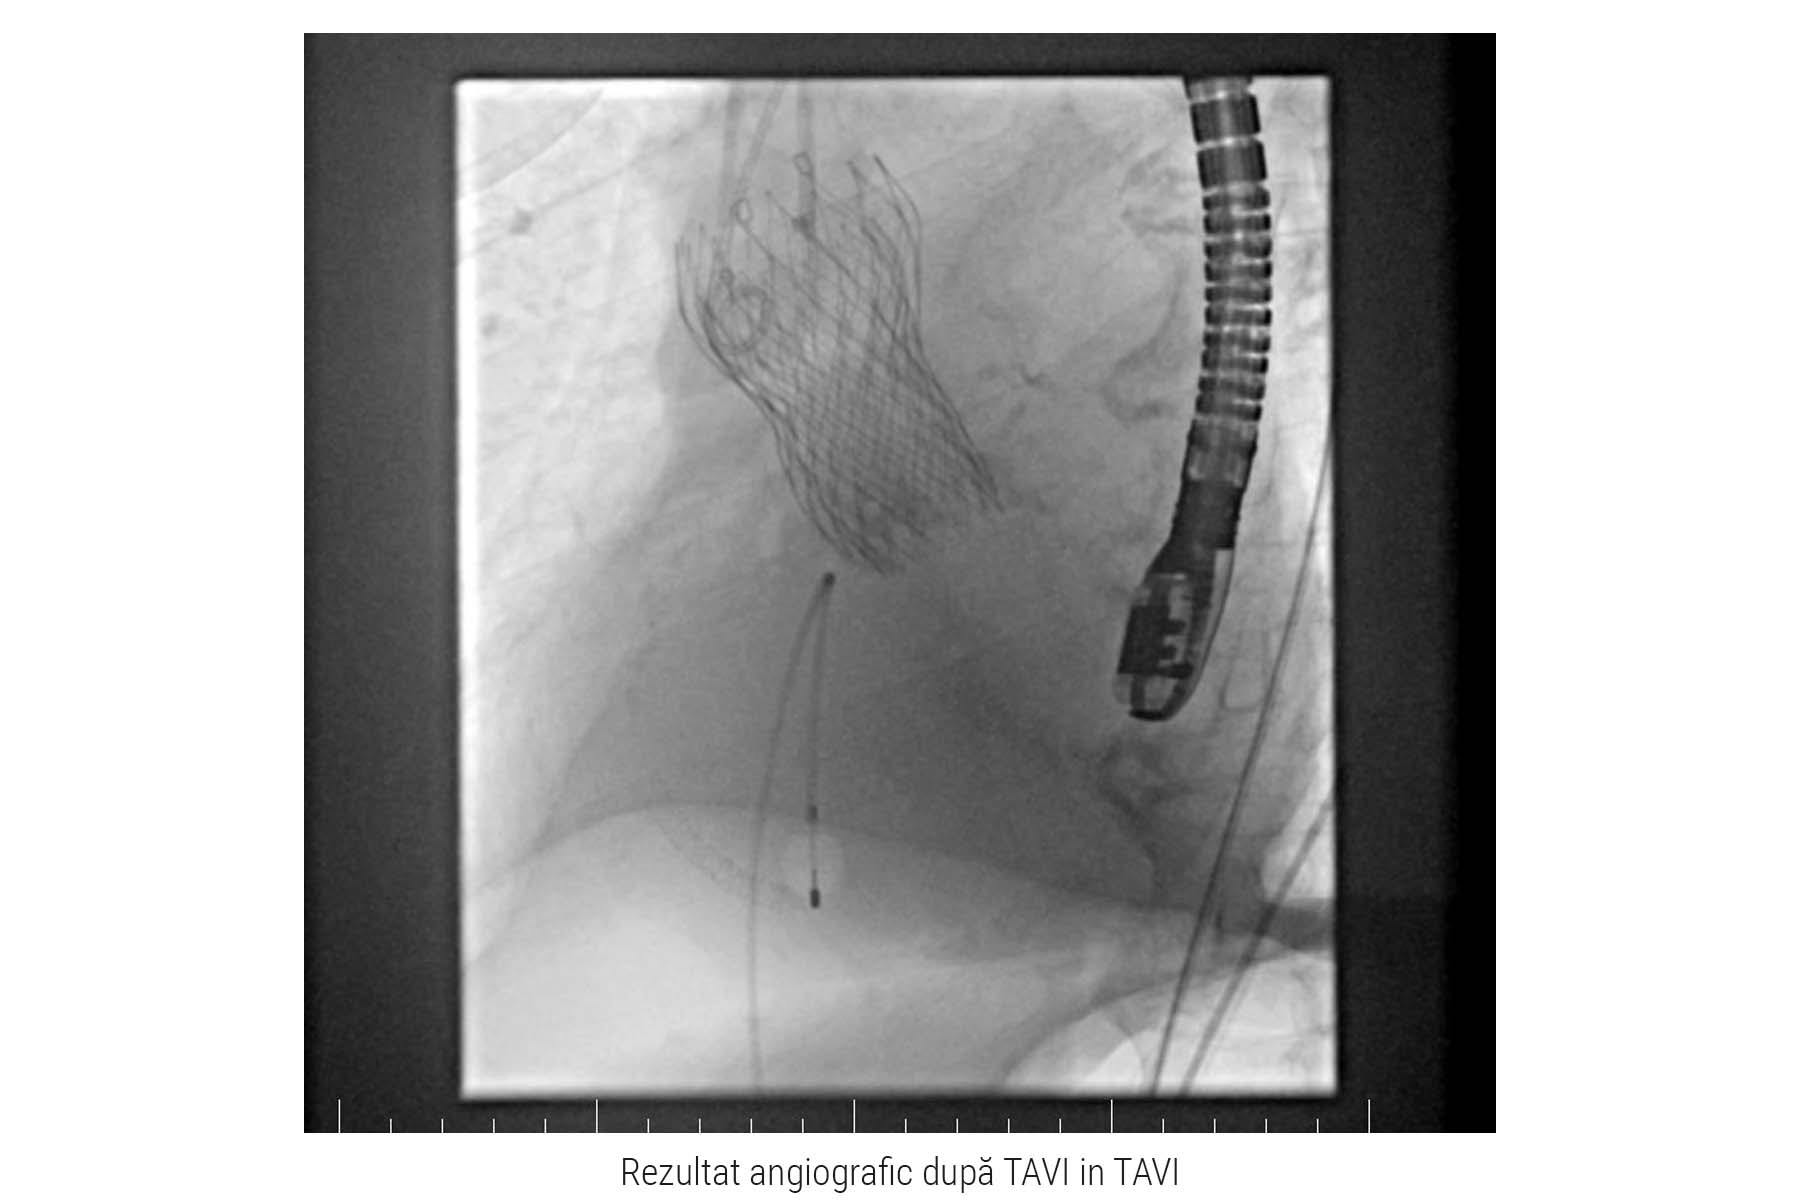

În luna februarie, la Centrul ARES din Spitalul Monza a avut loc o premieră medicală națională. Echipa multidisciplinară Heart Team formată din chirurgi cardiovasculari, cardiologi intervenționiști și cardiologi clinicieni a tratat cu succes un pacient în vârstă de 89 de ani cu regurgitare aortică severă într-o proteză TAVI degenerată, implantată în urmă cu 7 ani. Premiera a constat în implantarea unei proteze autoexpandabile tip Evolut Pro Plus, în proteza autoexpandabilă existentă, de tip Corevalve, montată anterior în poziție aortică.

Procedura TAVI în TAVI a fost efectuată sub anestezie generală și ghidaj ecografic transesofagian, prin abord transfemural ceea ce presupune o puncție în artera femurală, localizată la rădăcina coapsei piciorului. După ce a fost efectuată puncția, medicii au introdus catetere speciale și au ghidat proteza valvulară în formă compactă până la nivelul protezei existente. Aici au efectuat măsurători pentru poziționarea exactă a dispozitivului și au efectuat manevre medicale pentru expandarea și fixarea acesteia.

Rezultatul procedurii este unul extrem de bun, nu au fost complicații intra sau postprocedurale, pacientul a rămas sub supraveghere medicală pentru câteva zile. Pe întreaga perioadă a spitalizării, medicii au observat o evoluție favorabilă sub tratamentul medicamentos și îmbunătățirea simptomatologiei pacientului.